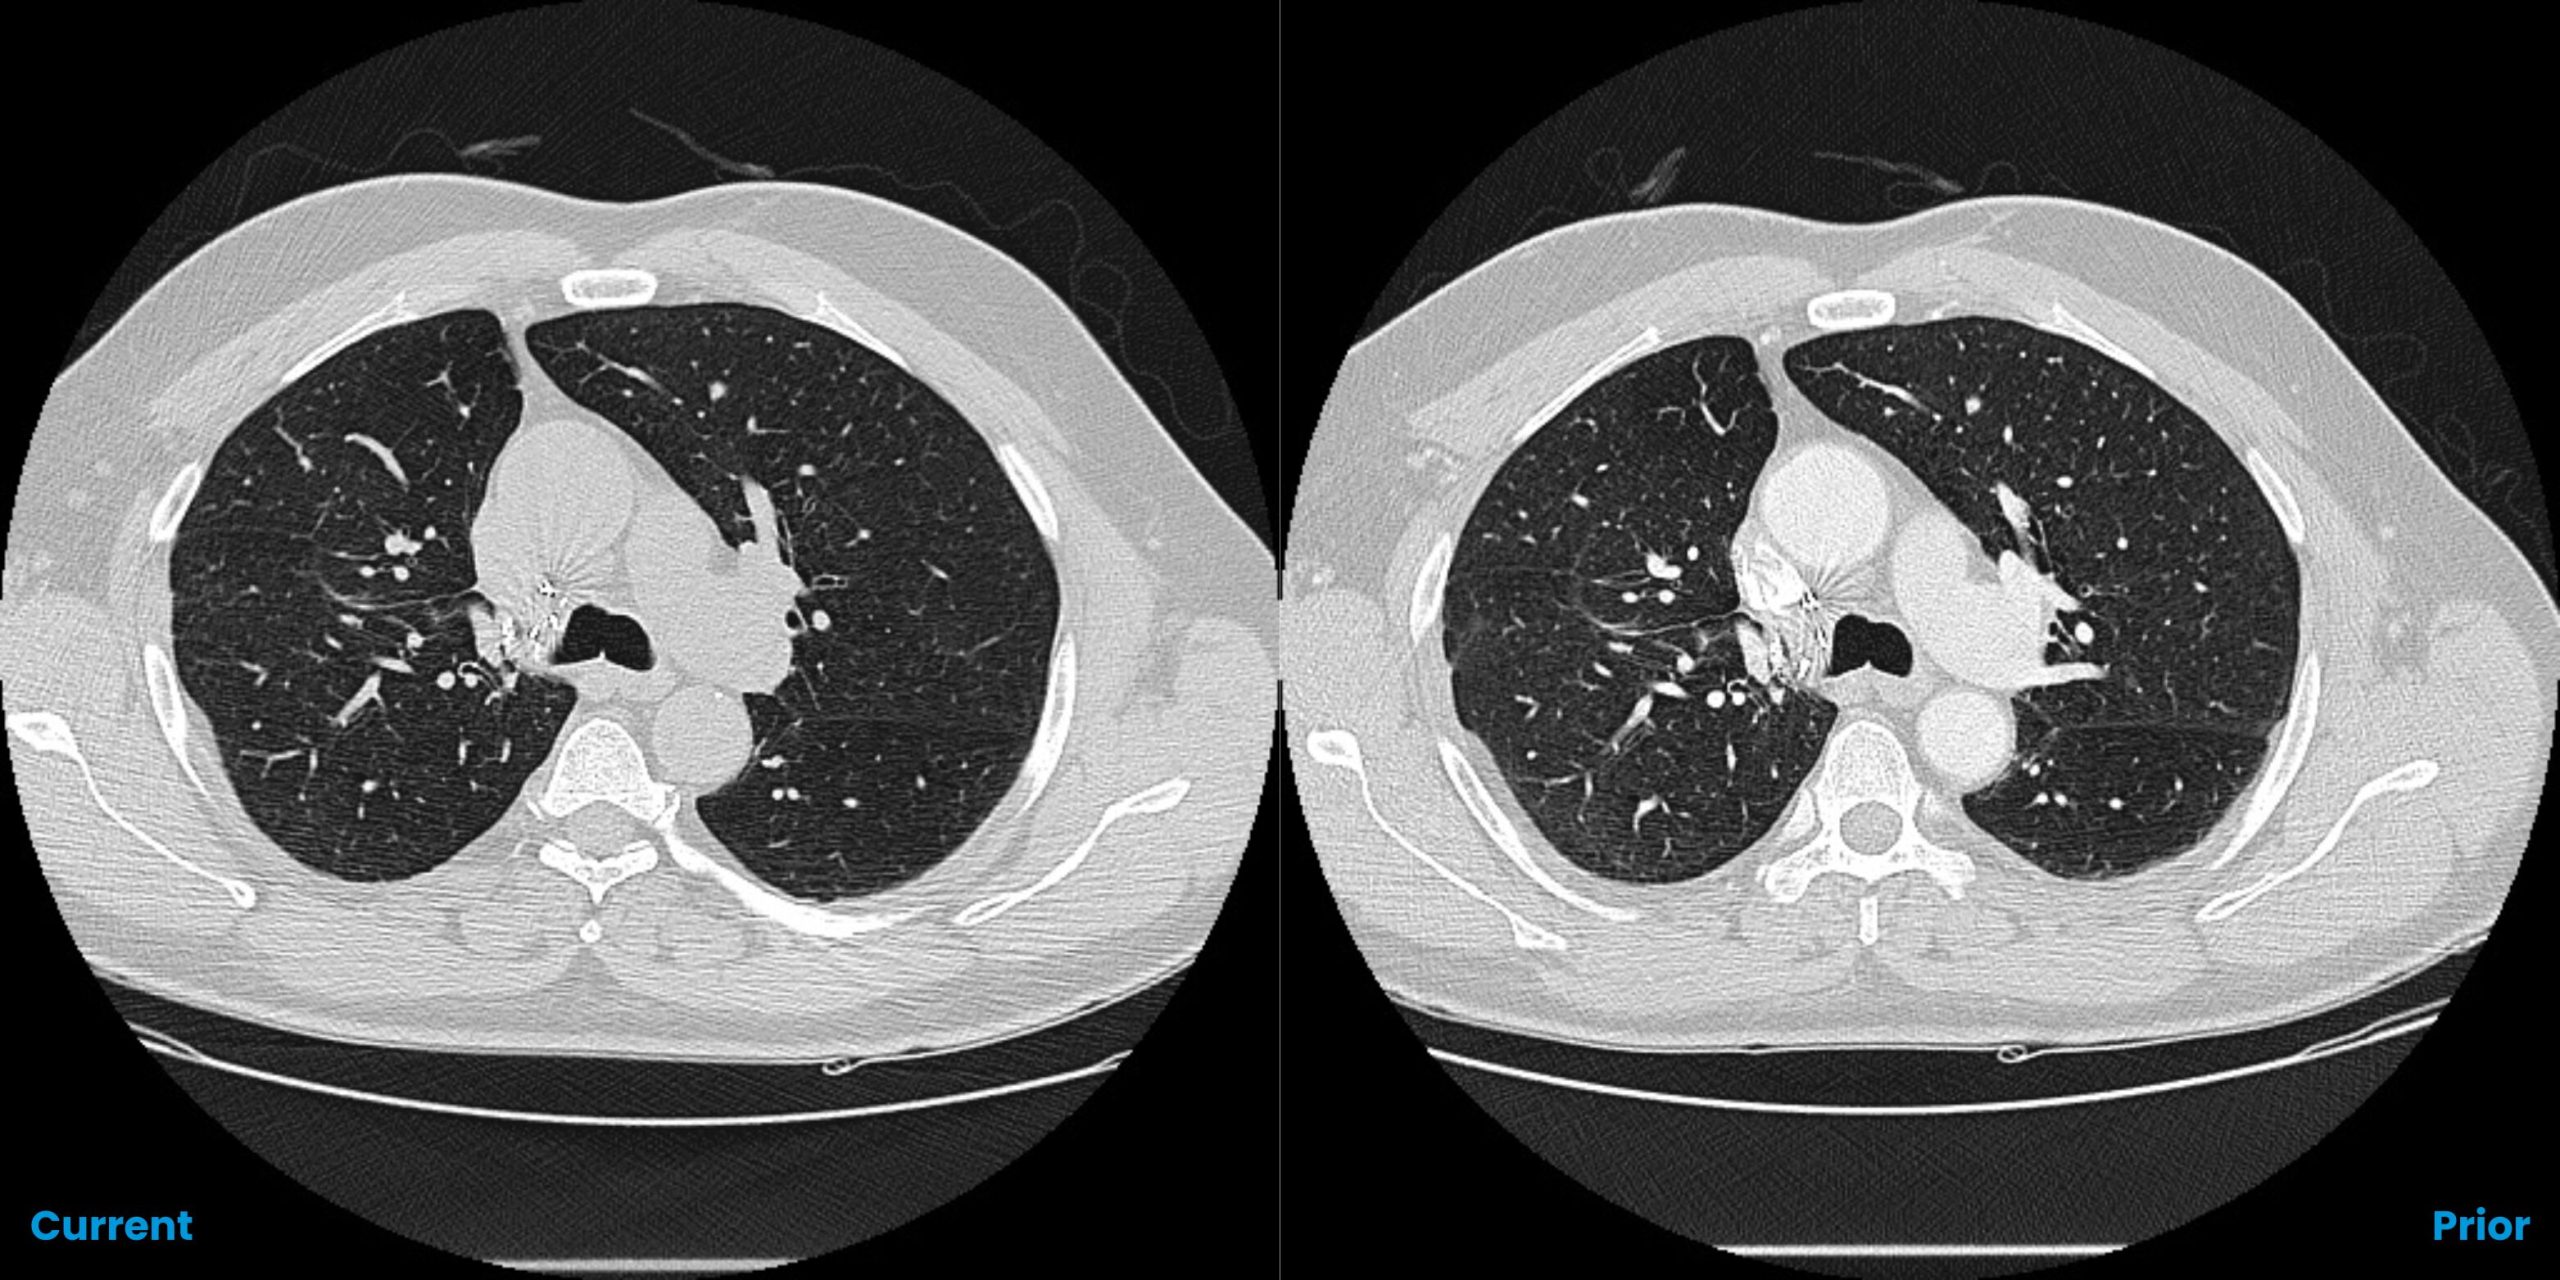

Pulmonary Nodules Automated nodule analysis, current and prior, and reporting to lighten cognitive load

- Quickly & easily compare nodule findings with prior exams – monitor changes in volume, diameter, and doubling time